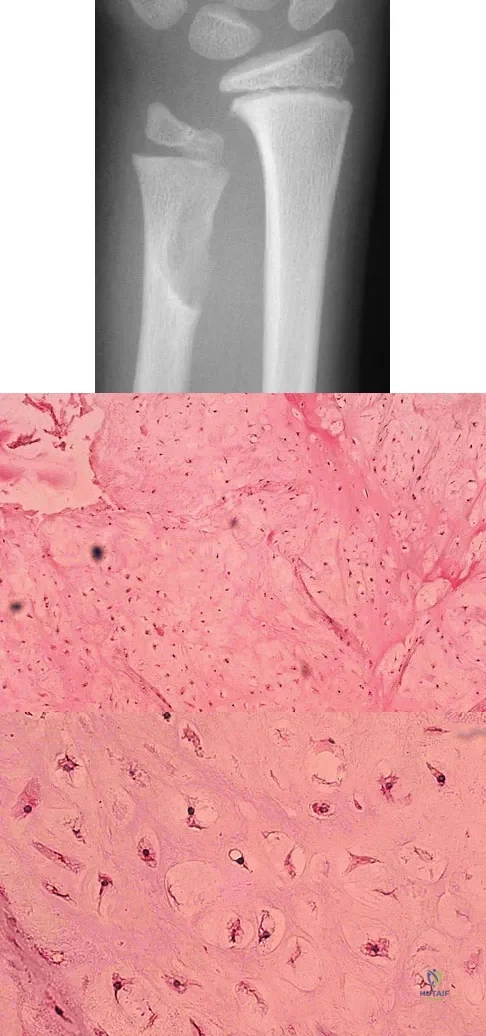

A 10-year-old boy has had wrist pain for the past 3 months. He denies any history of trauma. He reports mild tenderness associated with a palpable mass. A radiograph and biopsy specimens are shown in Figures 52a through 52c. What is the most likely diagnosis?

Explanation